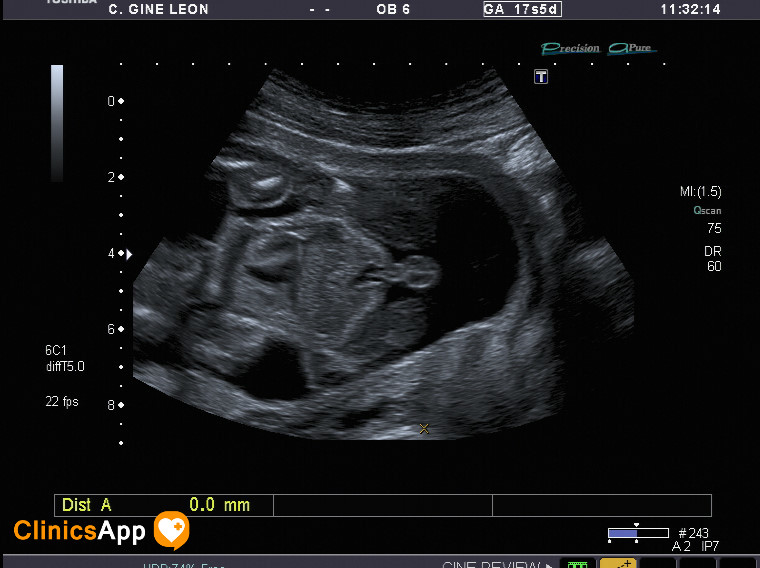

Tercera ecografía (parece que es un niño) Aquí tenemos las fotos de la ecografía de hoy. Parece ser que es un niño, ya no quedan muchas dudas. Fecha publicación 04/05/2016 Publicada por papá Publicada en Fotos, Galerías, Prenatal, Vídeos Comentarios 0 Entrada anterior: Segunda ecografía (mismo día por la tarde), ¡y con vídeo! Entrada siguiente: Cuarta ecografía ¡en 3D! Deja una respuesta Cancelar la respuestaComentario * Nombre * Correo electrónico * Web Guarda mi nombre, correo electrónico y web en este navegador para la próxima vez que comente. Recibir un correo electrónico con los siguientes comentarios a esta entrada. Δ